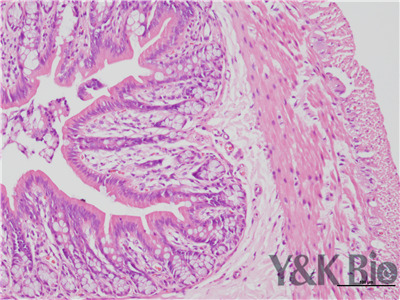

HE染色流程是什么,很多人都不知道,今天跟着小编一起来学习一下,切片的好坏直接影响疾病诊断的及时与准确性。因此一张高质量的HE染色切片,是实验室必须掌握的技术之一。HE染色目前在国内国外病理诊断上被

广泛采用,常规的染色方法。下面一起来看HE染色的基本顺序。一般切片的片子应在60-70度左右的烤箱中烘烤30分钟以才可以进行染色。总的来说是一个时间较长的过程。

1.样品制备

对于贴壁生长细胞,胰酶消化,调整细胞浓度约1×105/ml,滴加于盖玻片上(置于6孔板中),培养相应时间后,取出细胞爬片,用PBS 洗涤3次。2.样品固定 95%乙醇固定20min,PBS洗涤2次,每次1min。3.染核 苏木

素染液染色2-3min,自来水洗涤。4.分色 镜下观察,若细胞核染色过深,用1%盐酸酒精溶液分色数秒,自来水洗涤。 5.染胞质 浸入伊红染液染色1min,自来水洗涤。6.封片 吹干或自然晾干细胞爬片后,甘肃中性树胶封片。

以上六点就是HE染色的基本步骤,大家可以参考一下哦 。